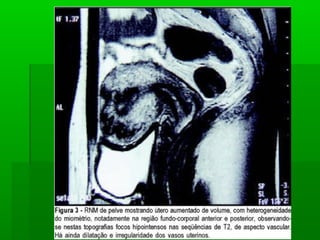

Quadro clínicoQuadro clínico

 Gravidez recente, especialmente seGravidez recente, especialmente se

molar;molar;

 Útero permanentemente aumentado;Útero permanentemente aumentado;

 Sangramento resistente ou curetagensSangramento resistente ou curetagens

repetidas.repetidas.